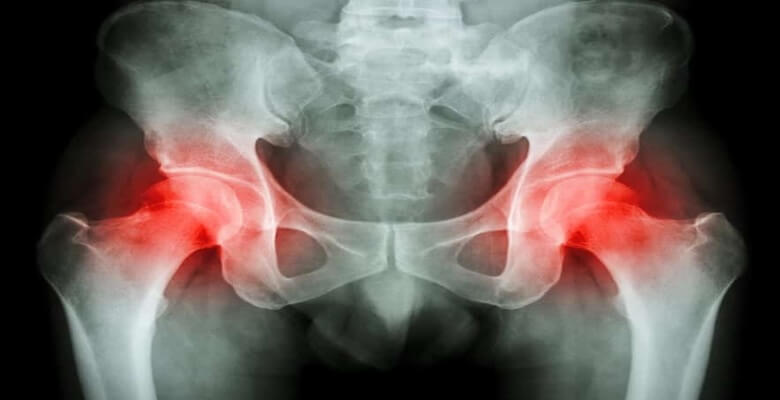

Tıbbi adıyla kalça osteoartriti, kalça ekleminde kıkırdak dokusunun aşınması ve bozulmasıyla ortaya çıkan bir eklem hastalığıdır. Kıkırdak dokusu eklem yüzeylerini kaplar ve kemiklerin sürtünmesini engelleyerek rahat hareket etmeyi sağlar. Ancak zamanla bu doku inceldiğinde veya zarar gördüğünde kemikler birbirine sürtünmeye başlar, bu da ağrı, sertlik ve hareket kısıtlılığı gibi belirtilere neden olur.

Kalça bölgesinde yaygın olarak görülen hastalıklar arasında kireçlenme (osteoartrit), bursit, femur başı avasküler nekrozu ve piriformis sendromu bulunur. Osteoartrit, eklemde kıkırdak kaybıyla ağrı ve sertliğe yol açar. Bursit, kalçadaki bursaların iltihaplanmasıyla oluşur. Avasküler nekroz, kalça kemiğine kan akışının kesilmesi sonucu gelişir. Piriformis sendromu ise siyatik sinirin sıkışmasına neden olarak ağrıya sebep olur.